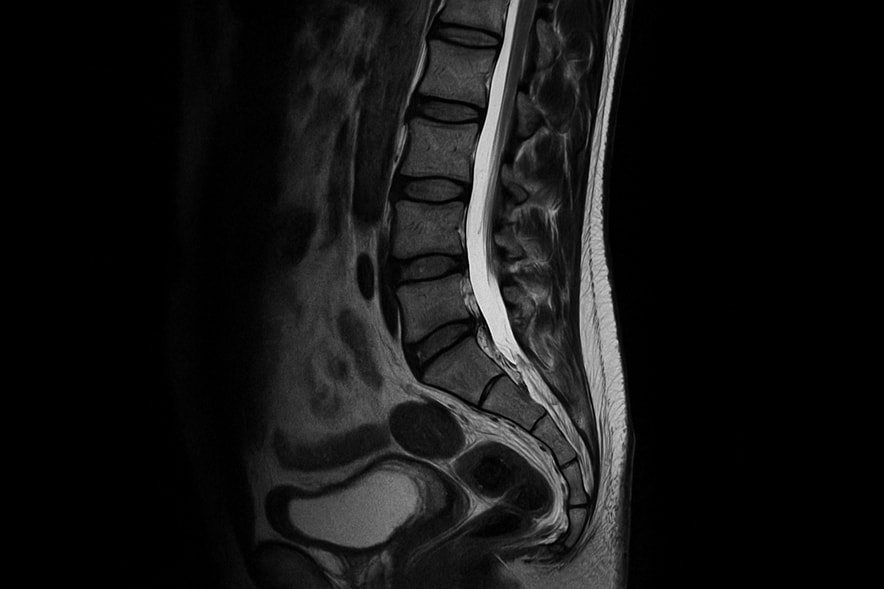

МРТ копчика — это современный и безопасный метод неинвазивной диагностики, который применяется для детальной оценки состояния нижнего отдела позвоночника. Исследование позволяет врачу рассмотреть структуры, невидимые на обычных рентгеновских снимках: мягкие ткани, связки, нервы, хрящи, сосуды и костные элементы.

Магнитно-резонансная томография копчика формирует изображение послойно, что помогает выявить патологии даже на ранних стадиях. Метод особенно ценен для пациентов, страдающих от хронических болей, последствий падений или воспалений в области таза и поясницы.

С помощью современных томографов врачи получают точные изображения копчикового отдела, на которых видны малейшие отклонения от нормы: микротрещины, воспаления, гематомы, деформации и новообразования. При подозрении на заболевания позвоночника обследование позволяет уточнить диагноз, исключить компрессию нервных волокон и определить состояние суставов.

Проведение обследования полностью безболезненно. Пациент ложится на выдвижной стол, тело фиксируется мягкими ремнями для предотвращения случайных движений. МРТ копчика выполняется на современных томографах, которые формируют послойные снимки за счет магнитного поля и радиоволн. Эти методы диагностики позволяют изучить анатомию копчикового отдела в мельчайших деталях, выявив даже микроскопические повреждения.